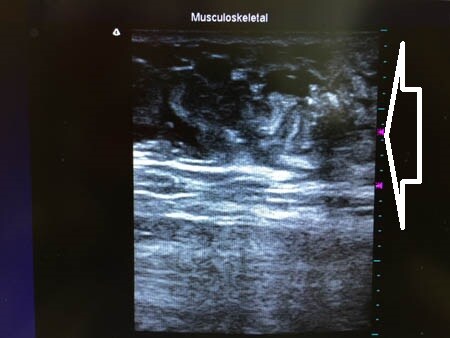

上の画像の部分をつまんでみましょう。